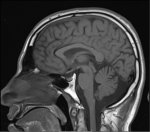

Нет, не влияет. Мозг в черепе может как угодно сидеть и соотношение между долями может быть разное.

А вот общий размер головы влияет, от него зависит размер мозга, а значит и интеллект. Но тут тоже есть свои нюансы, компоновка нейронов может быть разная и иногда даже в маленькой башке могут быть крутые структуры (но редко и прям гением точно не будешь тк у гениев в большой голове крутые структуры и 2кг ебать нейронов).

>3 пик

Нет не влияет. Пик4 вообще брахецефал и должен быть по черепометрительной логике ебанатом ай-кью 80

На МРТ мозг одинаковый. Это нажбровные дуги крупнее только и всего.